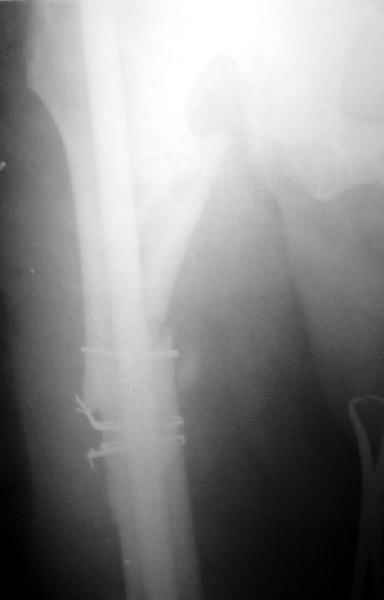

На данный момент правая голень срослась, больной активен в пределах постели. Второе(правое) бедро стабилизированное (рис. до и после). движения в коленном суставе: сгибательная контрактура правого коленного сустава 90, левого 145.

Наверное, мы привыкли, что штифт должен сидеть в костномозговом канале плотно. Гвоздь же этот, сидит относительно свободно, и это нас настораживает, не будет ли микроподвижность которая приведет к рецидиву ложного сустава.